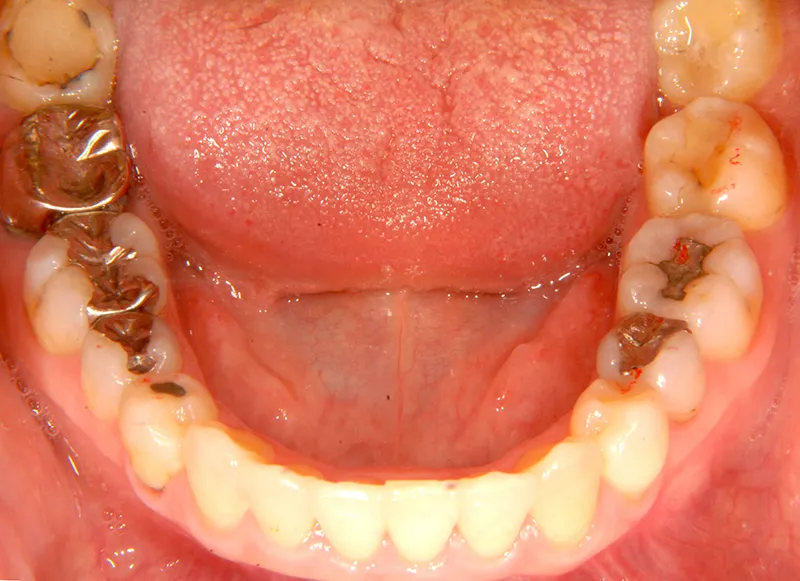

初診時年齢 40歳以上 (女性) 主訴 上下のがたがた・噛み合わない

診断名 叢生 装置名

上下のがたがたと噛み合わない事を主訴に来院されました。

歯は抜かずに矯正治療しました。

治療回数35回、2年8ヶ月の治療期間で矯正治療を終了しました。

噛み合わせが安定する事で、大きくなっていた咬筋が正常な大きさになり、顎のラインもシャープになり大変よろこばれていました。